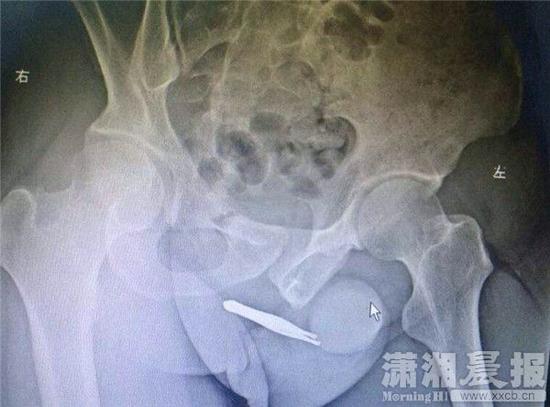

湖南男子把72毫米钳子塞入尿道:以为小便会排

407x550 - 28KB - JPEG

550x407 - 32KB - JPEG